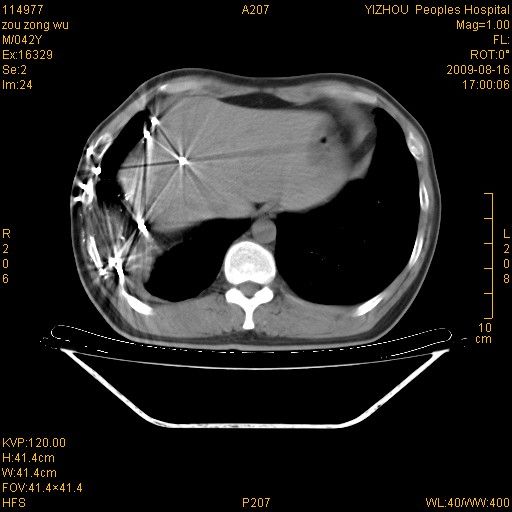

以下是引用zjzjr在2009-8-17 10:42:00的发言:[br]右侧间质性肺炎伴纤维化,右肺下叶肺囊肿伴感染(不除外外伤后引起),右肺野及胸壁软组织\\肝内见多发斑点状,中枪了吧.右侧胸膜肥厚\\粘连.